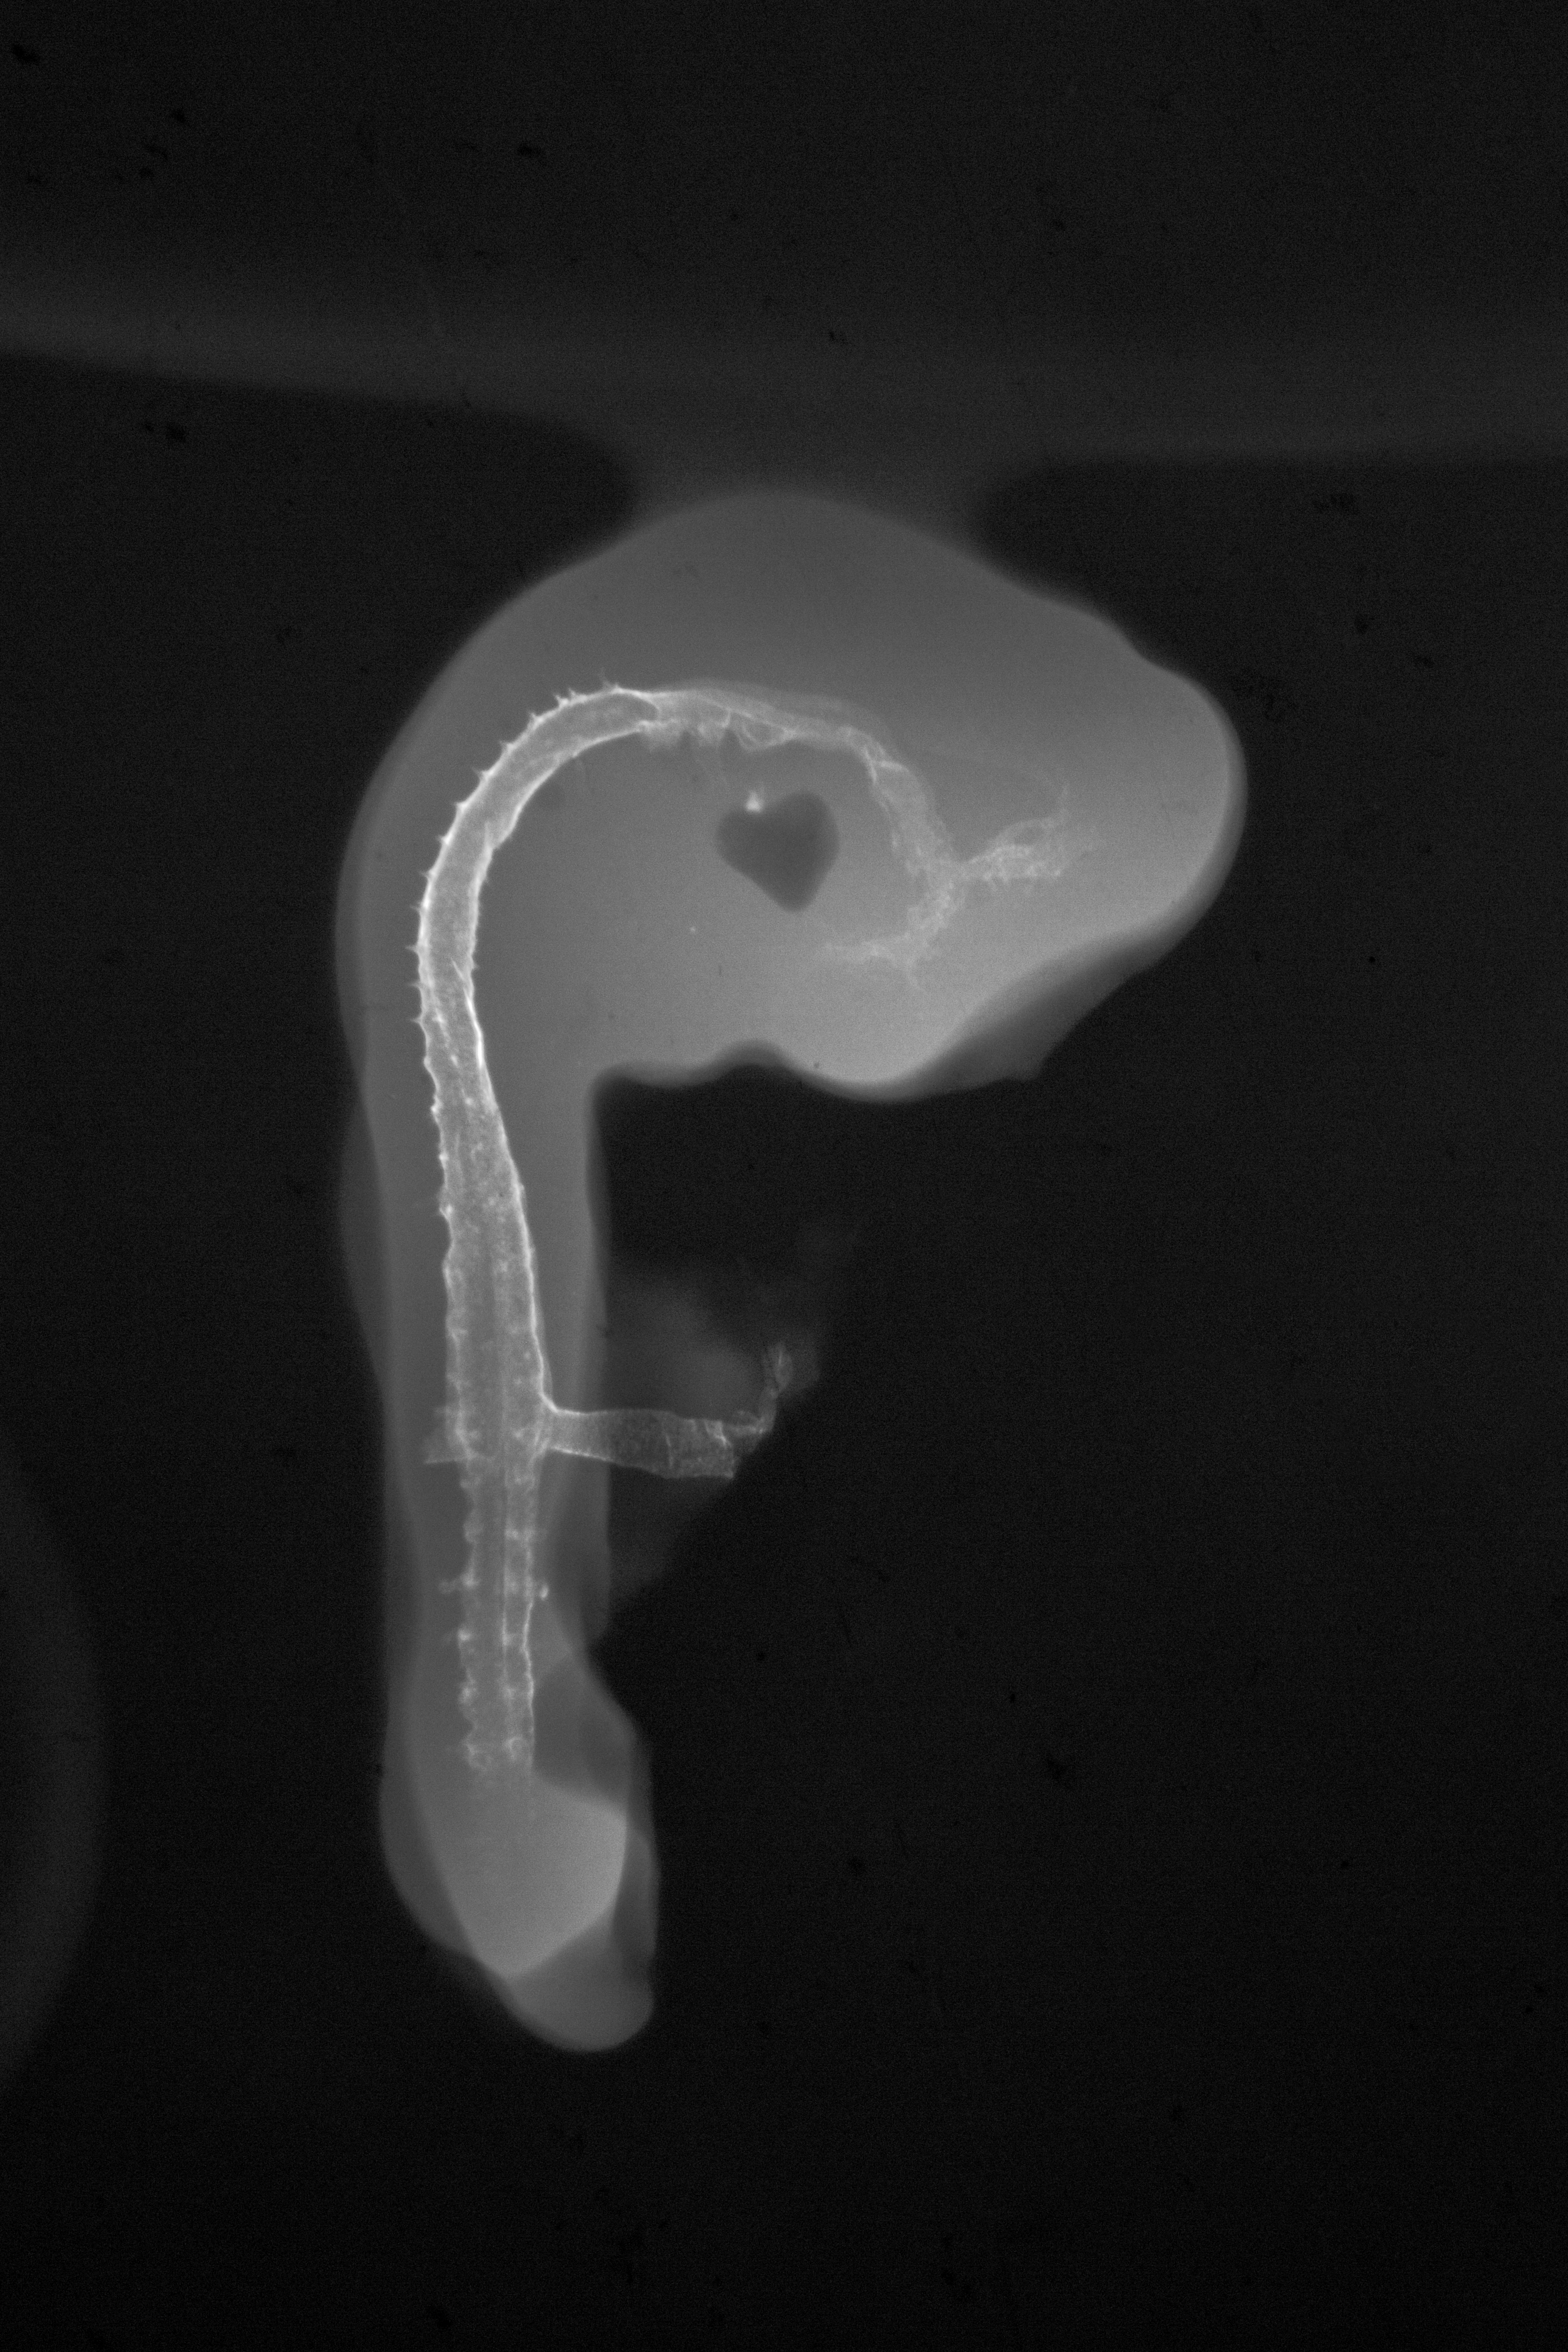

Chick Embryo Microangiography

Hamburger-Hamilton (HH) Stage 18 (approx. 3 days)

X-Ray Micrographs